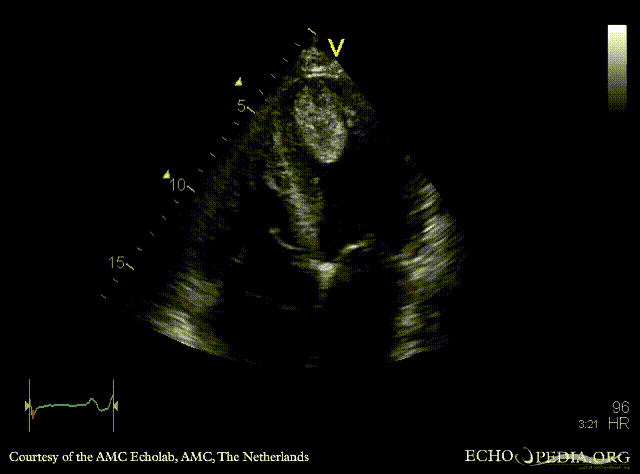

Case 142